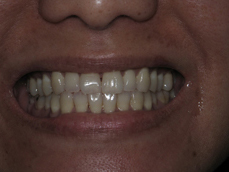

Orthodontic Treatment X-ray - After